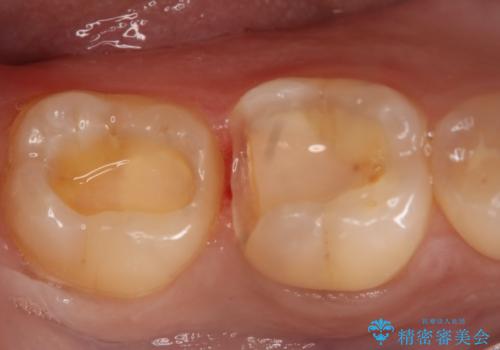

- 右下6・7番の治療のやり変えを主訴に来院された患者様です。

保険の材料が劣化し中で虫歯が進行しているため、古い材料と虫歯を全て除去した上で詰め直す必要がありました。

切削量・形態を考慮し、セラミックインレーでの治療を計画しました。